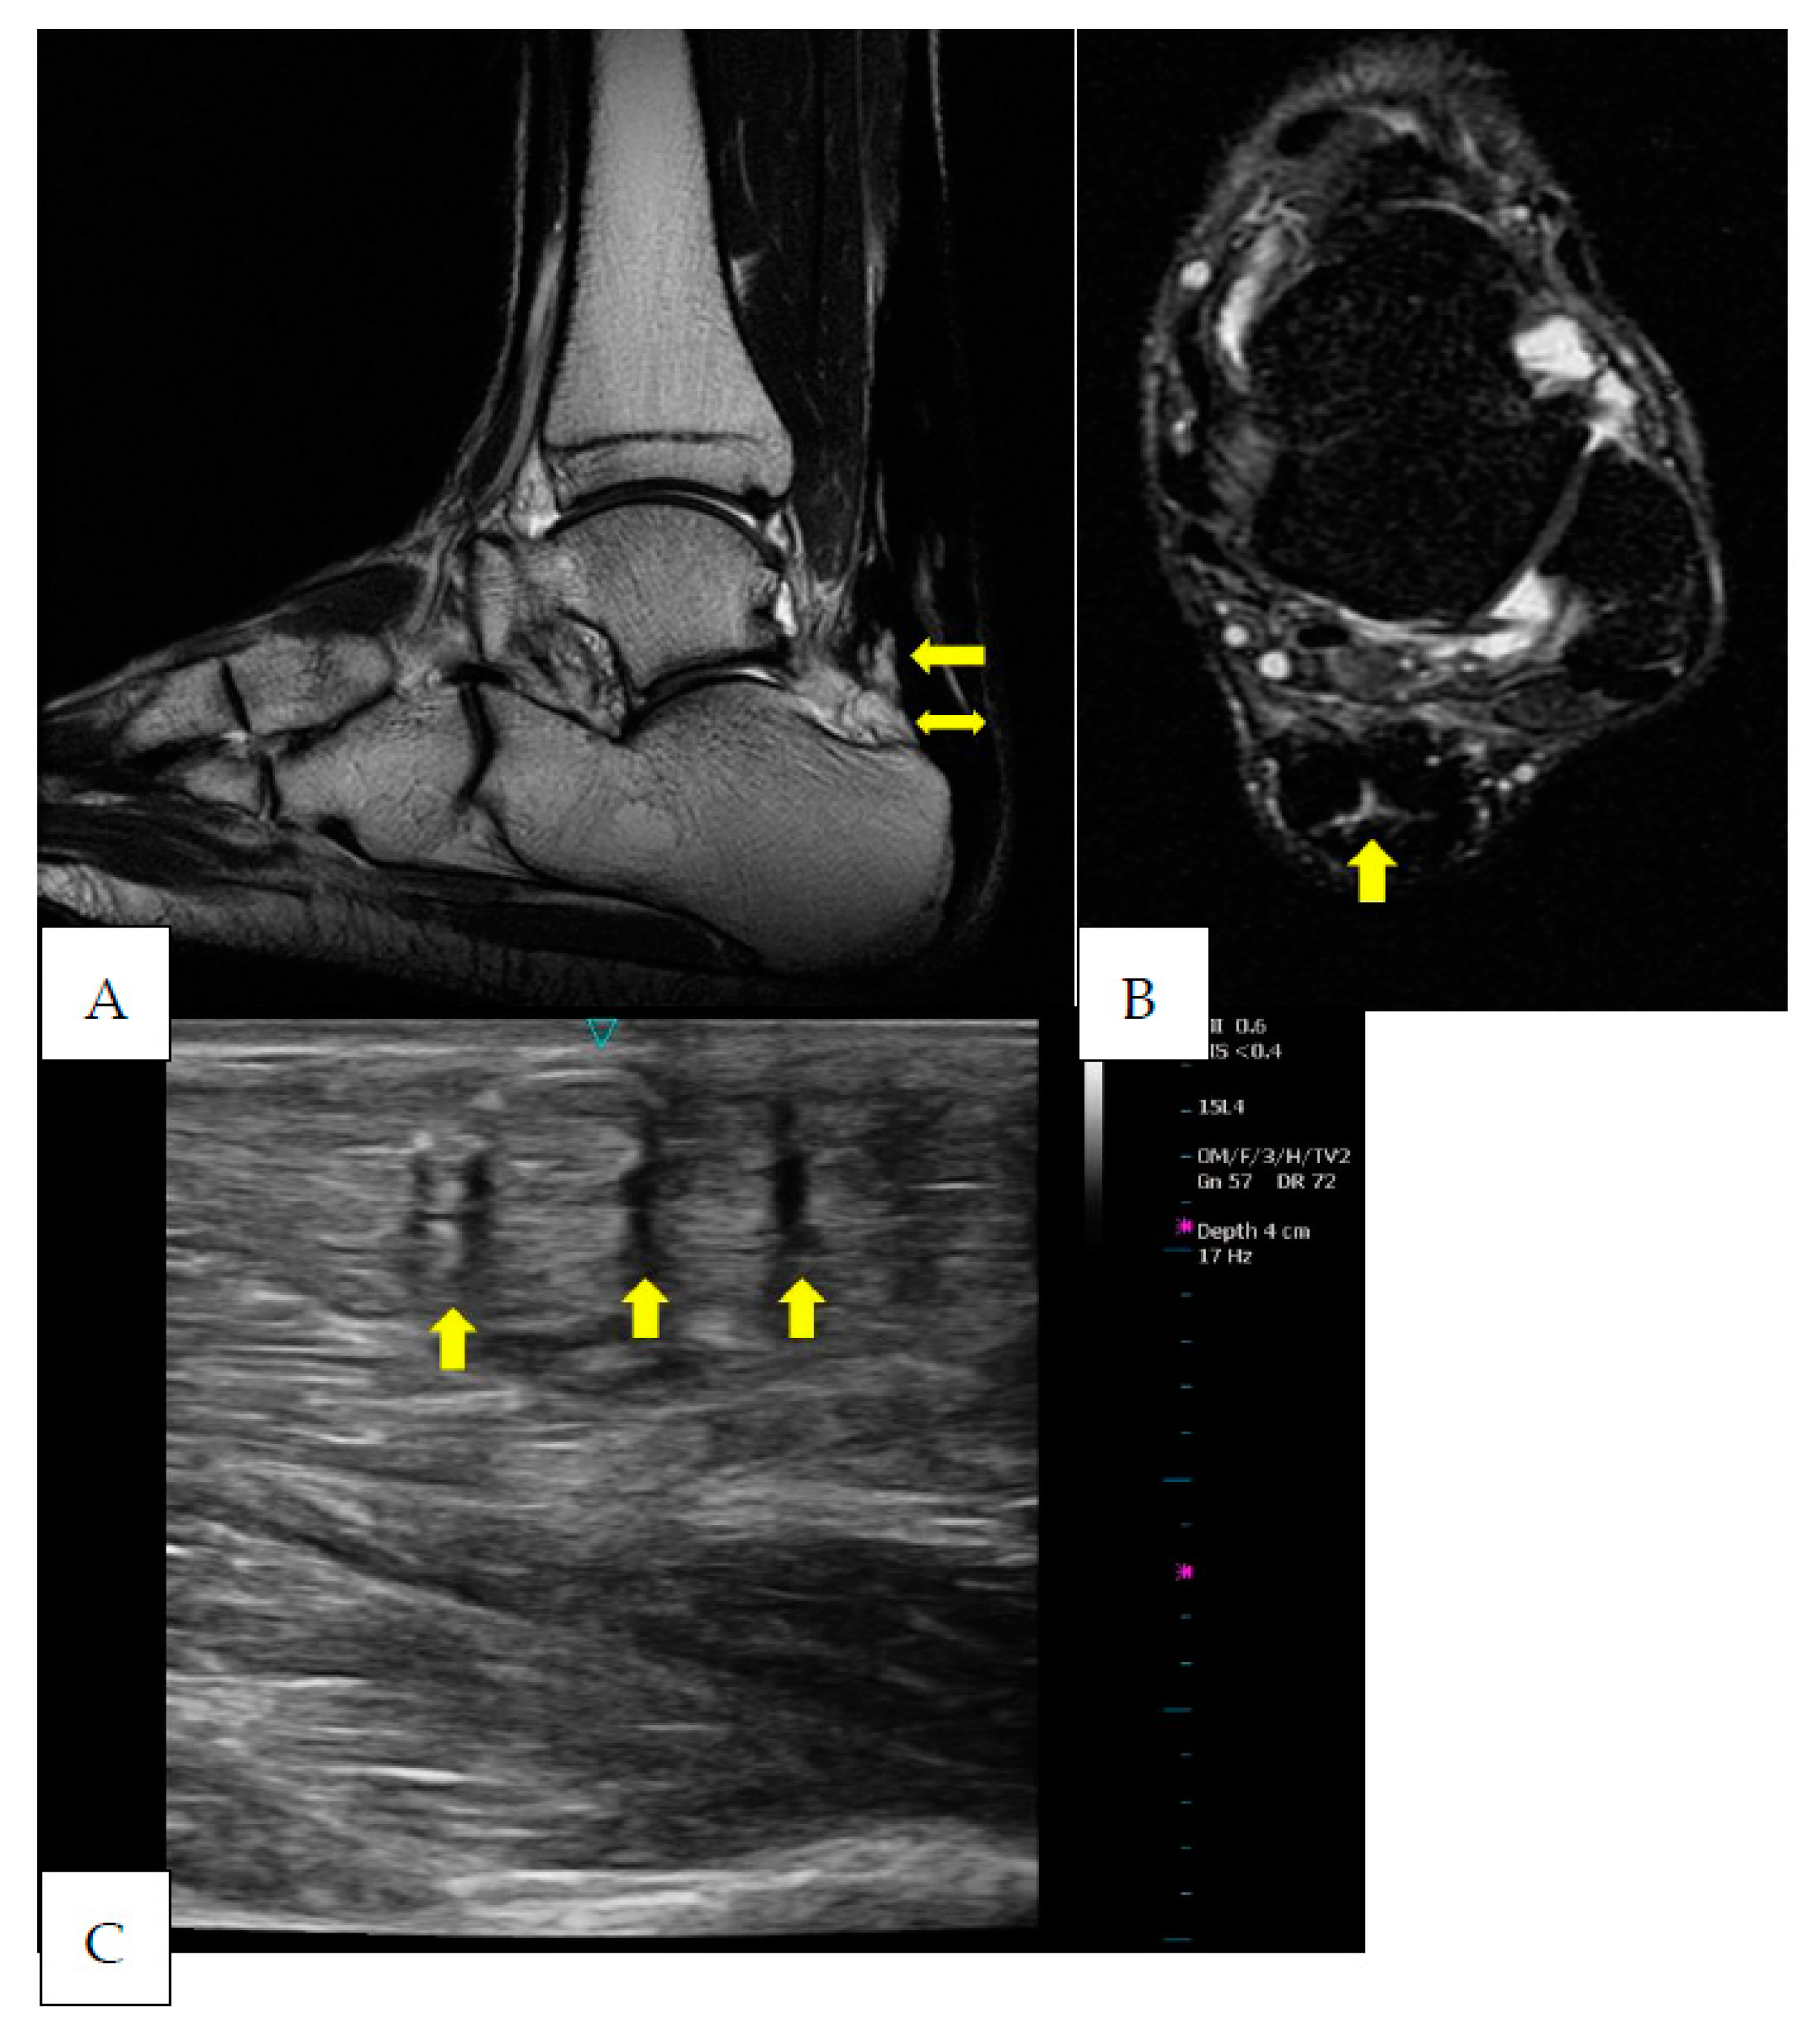

2. Case Presentation